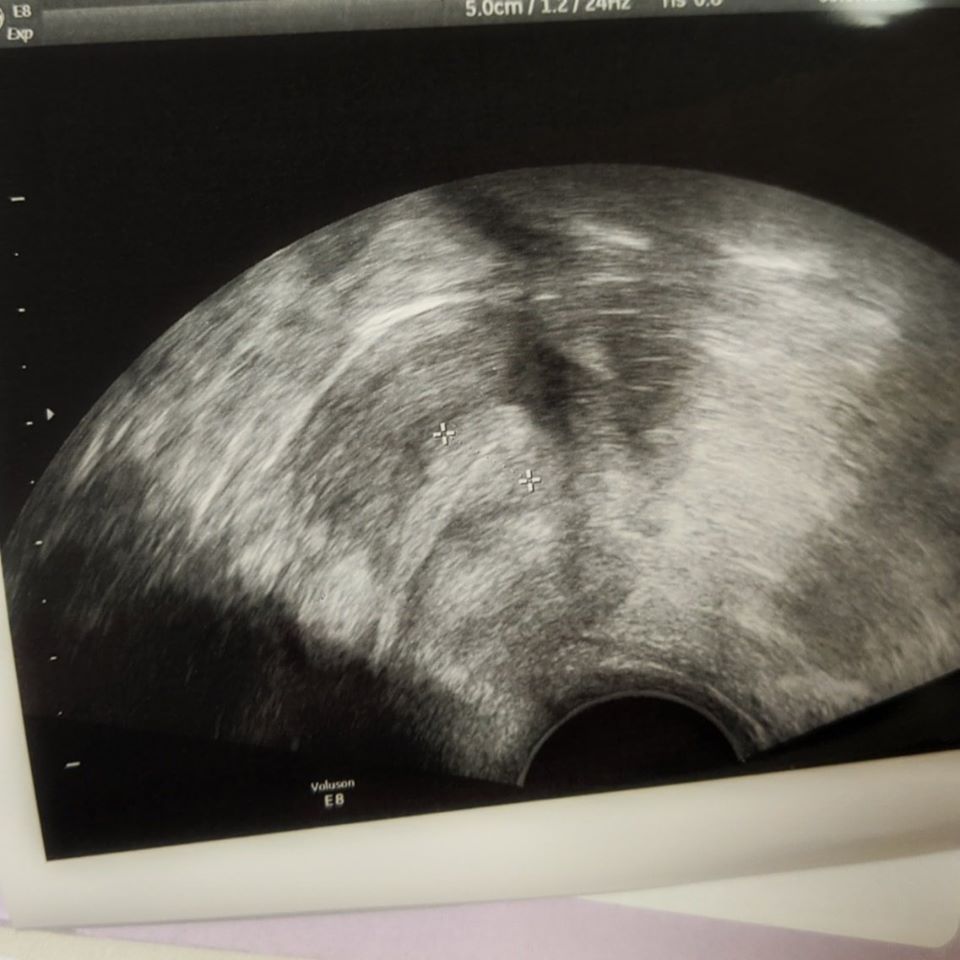

So on CD18 (or 19 depending on what my app said!) I headed to the clinic for a baseline scan and to check ovulation – the sonographer was lovely and found both ovaries fine! She showed me that I had a “collapsed follicle” which has a jagged edge – this shows that I ovulated and I said that I thought I had ovulated around CD 14 / 15 whichs she said was probably about right

I still had the 3-line / feathery uterus lining too – so everything was then good to go for my Nurse Consultation!